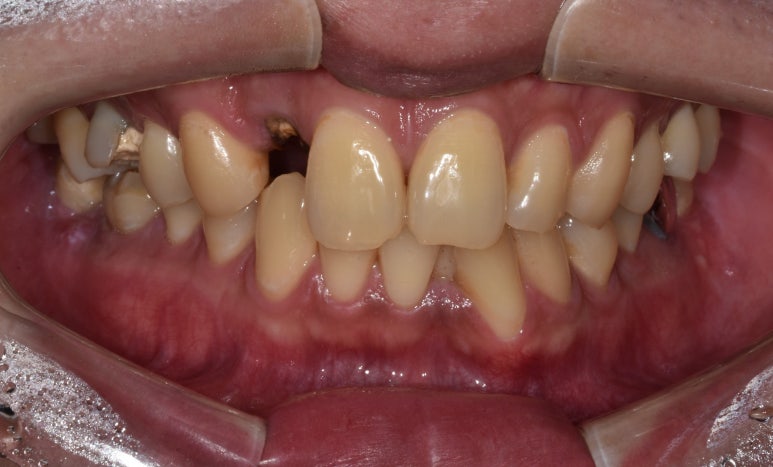

20대임플란트 실제 사례

25세 여성

(전) 2022-03-03 (후) 2022-10-11